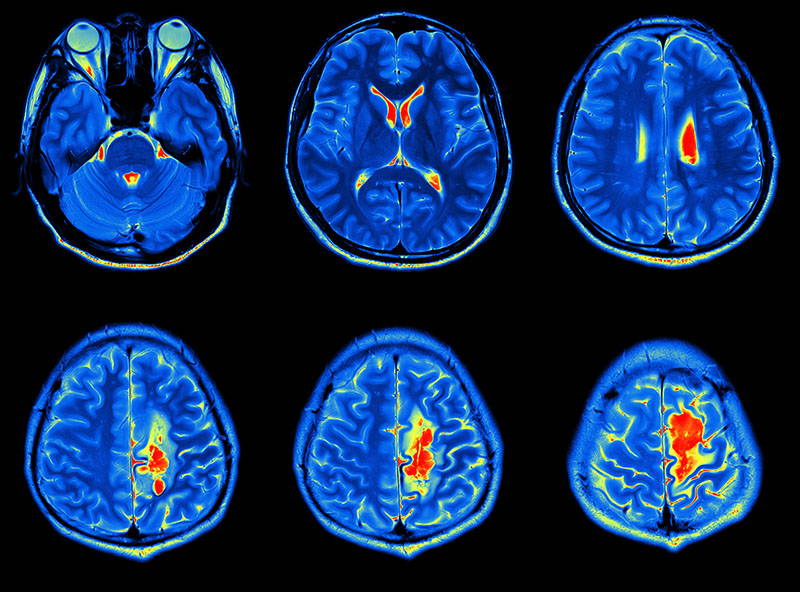

İstanbul Okan Üniversitesi Hastanesi Beyin ve Sinir Cerrahisi Uzmanı Doç. Dr. Ahmet Öğrenci, beyin tümörlerinin tanı ve tedavisi hakkında bilgilendirdi. Öğrenci'nin açıklamaları şöyle; Beyin kafatası içinde yer alan yumuşak kıvamda bir organdır. Birçok koordineli ve rastgele hareketin merkezidir. Bilinç ve duygusal yaşamın da merkezindedir. Hayati fonksiyonlarımızı kontrol eder. Bu nedenle, hayatımızın merkezindedir. Beyinle ilgili en ufak bir hastalık şüphesi, hastayı ciddi moral bozukluğuna ve depresyona itebilir. Ancak gerçek, öyle değildir. Beyinde yer alan her hastalık, kitle, kist her zaman ciddi sonuçlarla sonuçlanmaz.

En yaygın belirti baş ağrısı! Beyinde yer kaplayan hastalıklara baktığımızda bunların benign (iyi), malign (kötü) karakterlerde davranış gösterebildiğini söyleyebiliriz. Hastalar kitlenin bulunduğu yer ile ilgili fonksiyonel kayıplarla ve genel şikayetler ile doktora başvururlar. Hastalarda problemin başlamasının ana sebebi; kapalı bir alanda bulunan beyinde yani kafa içinde basıncın artmasıdır. En sık başvuru sebebi baş ağrısıdır. Sonrasında bulantı-kusma, şuur dalgalanmaları, uyku hali, baş dönmesi ve nöbet geçirme, vücudun farklı bölgelerinde kuvvetsizlikler, iştahsızlık, unutkanlık gelmektedir. Ancak şikayetler çok daha çeşitlilik gösterebilir. Hastalarda kitlenin bulunduğu yerin farklılığına göre dengesizlik, çift görme, görememe, yazılanı okuyamama, konuşamama, konuşulanı anlamama, yeni kelimeler ile konuşma, işitme bozuklukları, kulaklarda çınlama, kişilik değişiklikleri görülebilir. Bazılarında ise kafada şişlik, gözde dışarı doğru şişme, yüz felci gibi belirtiler olabilmektedir.